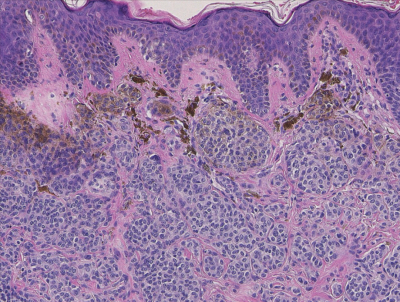

50 歳の男性。右頰部の皮疹を主訴に来院した。約 10 年前から徐々に隆起してきた。自然に出血はしない。瘙痒と疼痛はない。右鼻唇溝に直径 5 mm の隆起した黒褐色の結節を認める。右頸部リンパ節の腫脹は認めない。結節を切除した。術前の右鼻唇溝部の写真と切除検体の H-E 染色標本を別に示す。

診断はどれか。

a. Bowen 病

b. 悪性黒色腫

c. 基底細胞癌

d. 色素性母斑

e. 脂漏性角化症